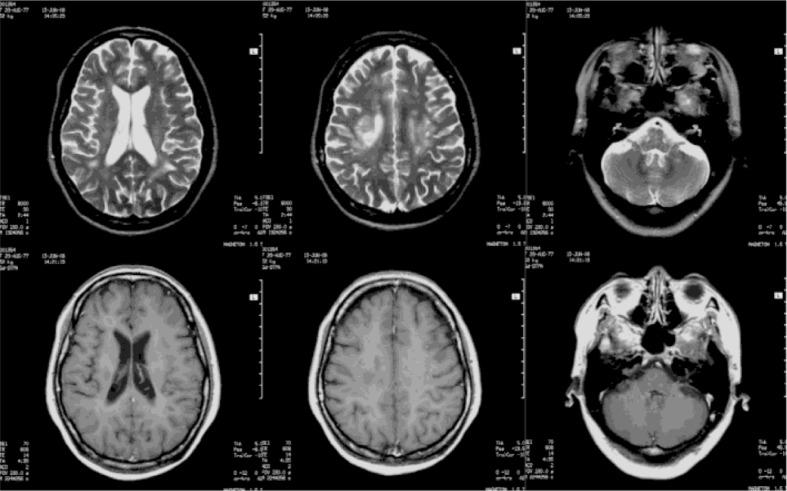

Pseudobulbar affect (PBA) is a common complication of central nervous system diseases such as stroke, multiple sclerosis, and other neurological diseases, but it remains under-recognized and under-treated in the clinic. PBA caused by acute disseminated encephalomyelitis (ADEM) has rarely been reported. Here, we report a 30-year-old Chinese woman who has experienced PBA from ADEM for 7 years. The patient's principal manifestations were extreme emotions or tears when she saw, heard, or spoke about sad news or other sad things; the durations of these unmanageable emotions were often less than 30 sec, and they occurred at frequencies that ranged from one to several times a day. Occasionally, she laughed uncontrollably while people were talking despite a lack of funny or sad stimuli in the conversation or the surrounding environment. Thus, her social functioning was impaired. This case indicates that the long-term PBA can occur secondarily to ADEM, and this possibility should be considered clinically to ensure timely identification and treatment.

假性延髓情绪(PBA)是中风、多发性硬化症等中枢神经系统疾病以及其他神经疾病的常见并发症,但在临床上仍未得到充分认识和治疗。急性播散性脑脊髓炎(ADEM)引起的PBA鲜有报道。在此,我们报告一名30岁的中国女性,她患ADEM引发的PBA已达7年。患者的主要表现为在看到、听到或谈论悲伤消息或其他悲伤事情时出现极端情绪或流泪;这些难以控制的情绪持续时间通常少于30秒,每天发生频率为1至几次。偶尔,在人们交谈时,尽管对话或周围环境中没有有趣或悲伤的刺激因素,她也会 uncontrollably 大笑。因此,她的社交功能受到了损害。该病例表明,长期PBA可继发于ADEM,临床上应考虑到这种可能性,以确保及时识别和治疗。 (注:原文中“uncontrollably”未翻译完整,应是“无法控制地”,但按照要求未添加解释)